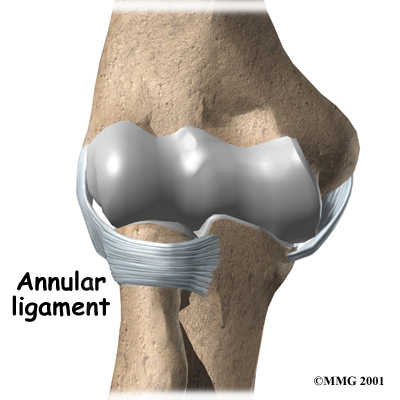

There are several important ligaments in the elbow. Ligaments are soft tissue structures that connect bones to bones. The ligaments around a joint usually combine together to form a joint capsule. A joint capsule is a watertight sac that surrounds a joint and contains lubricating fluid called synovial fluid.

In the elbow, two of the most important ligaments are the medial collateral ligament and the lateral collateral ligament. The medial collateral is on the inside edge of the elbow, and the lateral collateral is on the outside edge. Together these two ligaments connect the humerus to the ulna and radius, and keep the bones tightly in place as they move around the end of the humerus. These ligaments are the main source of stability for the elbow but can be torn when there is an injury or dislocation to the elbow. If they do not heal correctly the elbow can be too loose, or unstable.

There is also an important ligament called the annular ligament that wraps around the radial head and holds it tight against the ulna. The word annular means ring shaped, and the annular ligament forms a ring around the radial head as it holds it in place. This ligament can be torn when the entire elbow or just the radial head is dislocated.